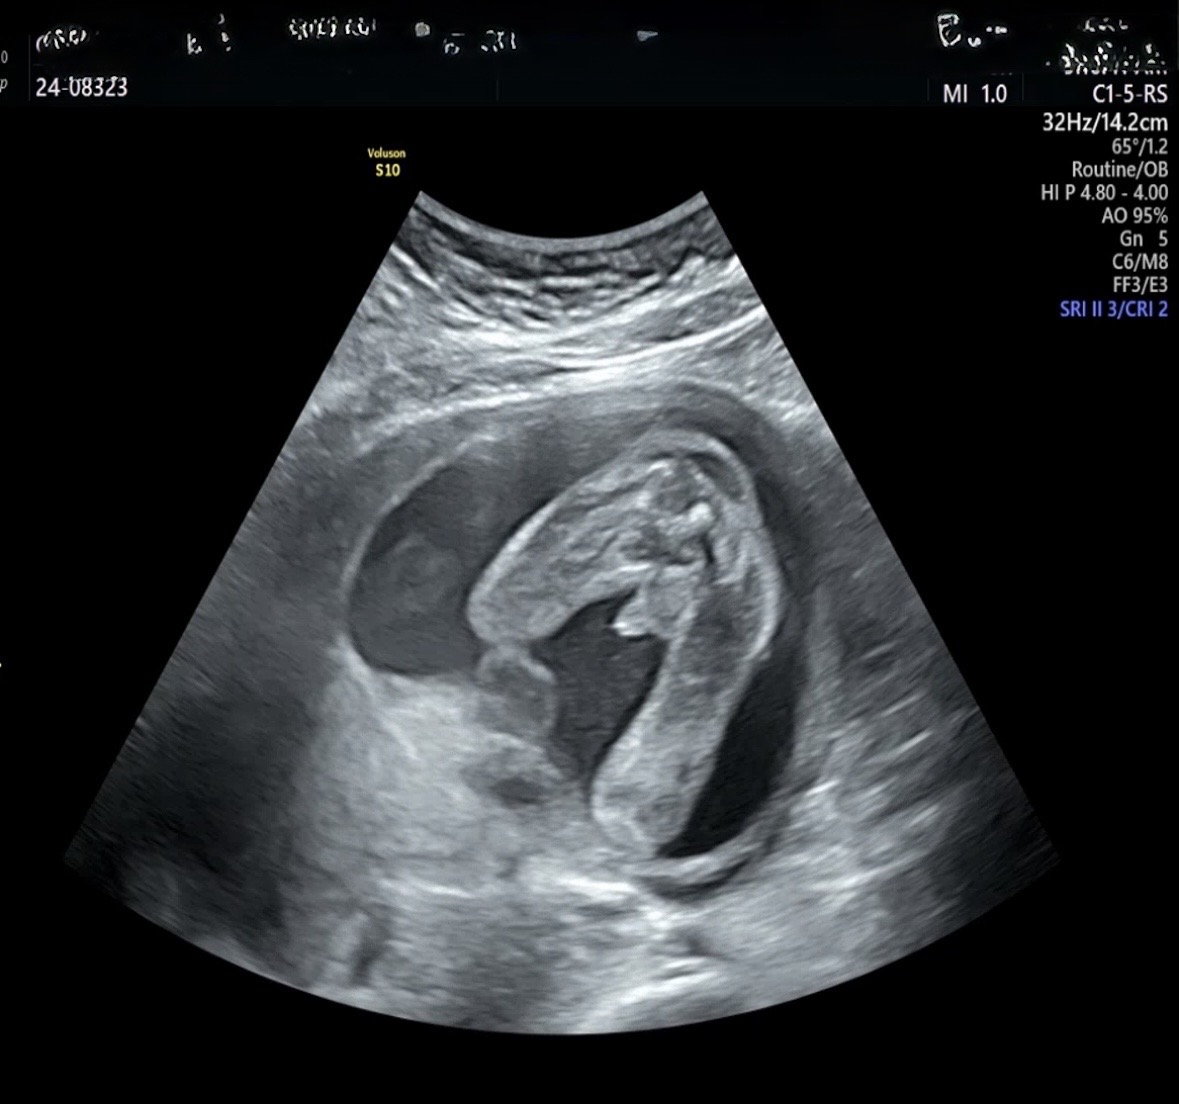

21주 아들맘

오늘 4주만에 진료보고 왔는데 첫 성별 알때도 오늘도 원장님이 ㄲㅊ가 크다며 mvp라며 막 여러번 보여주는데 왤케 부끄럽나여 … ㅋㅋㅋㅋㅌㅌㅋ 진짜 큰편이에요 ..?